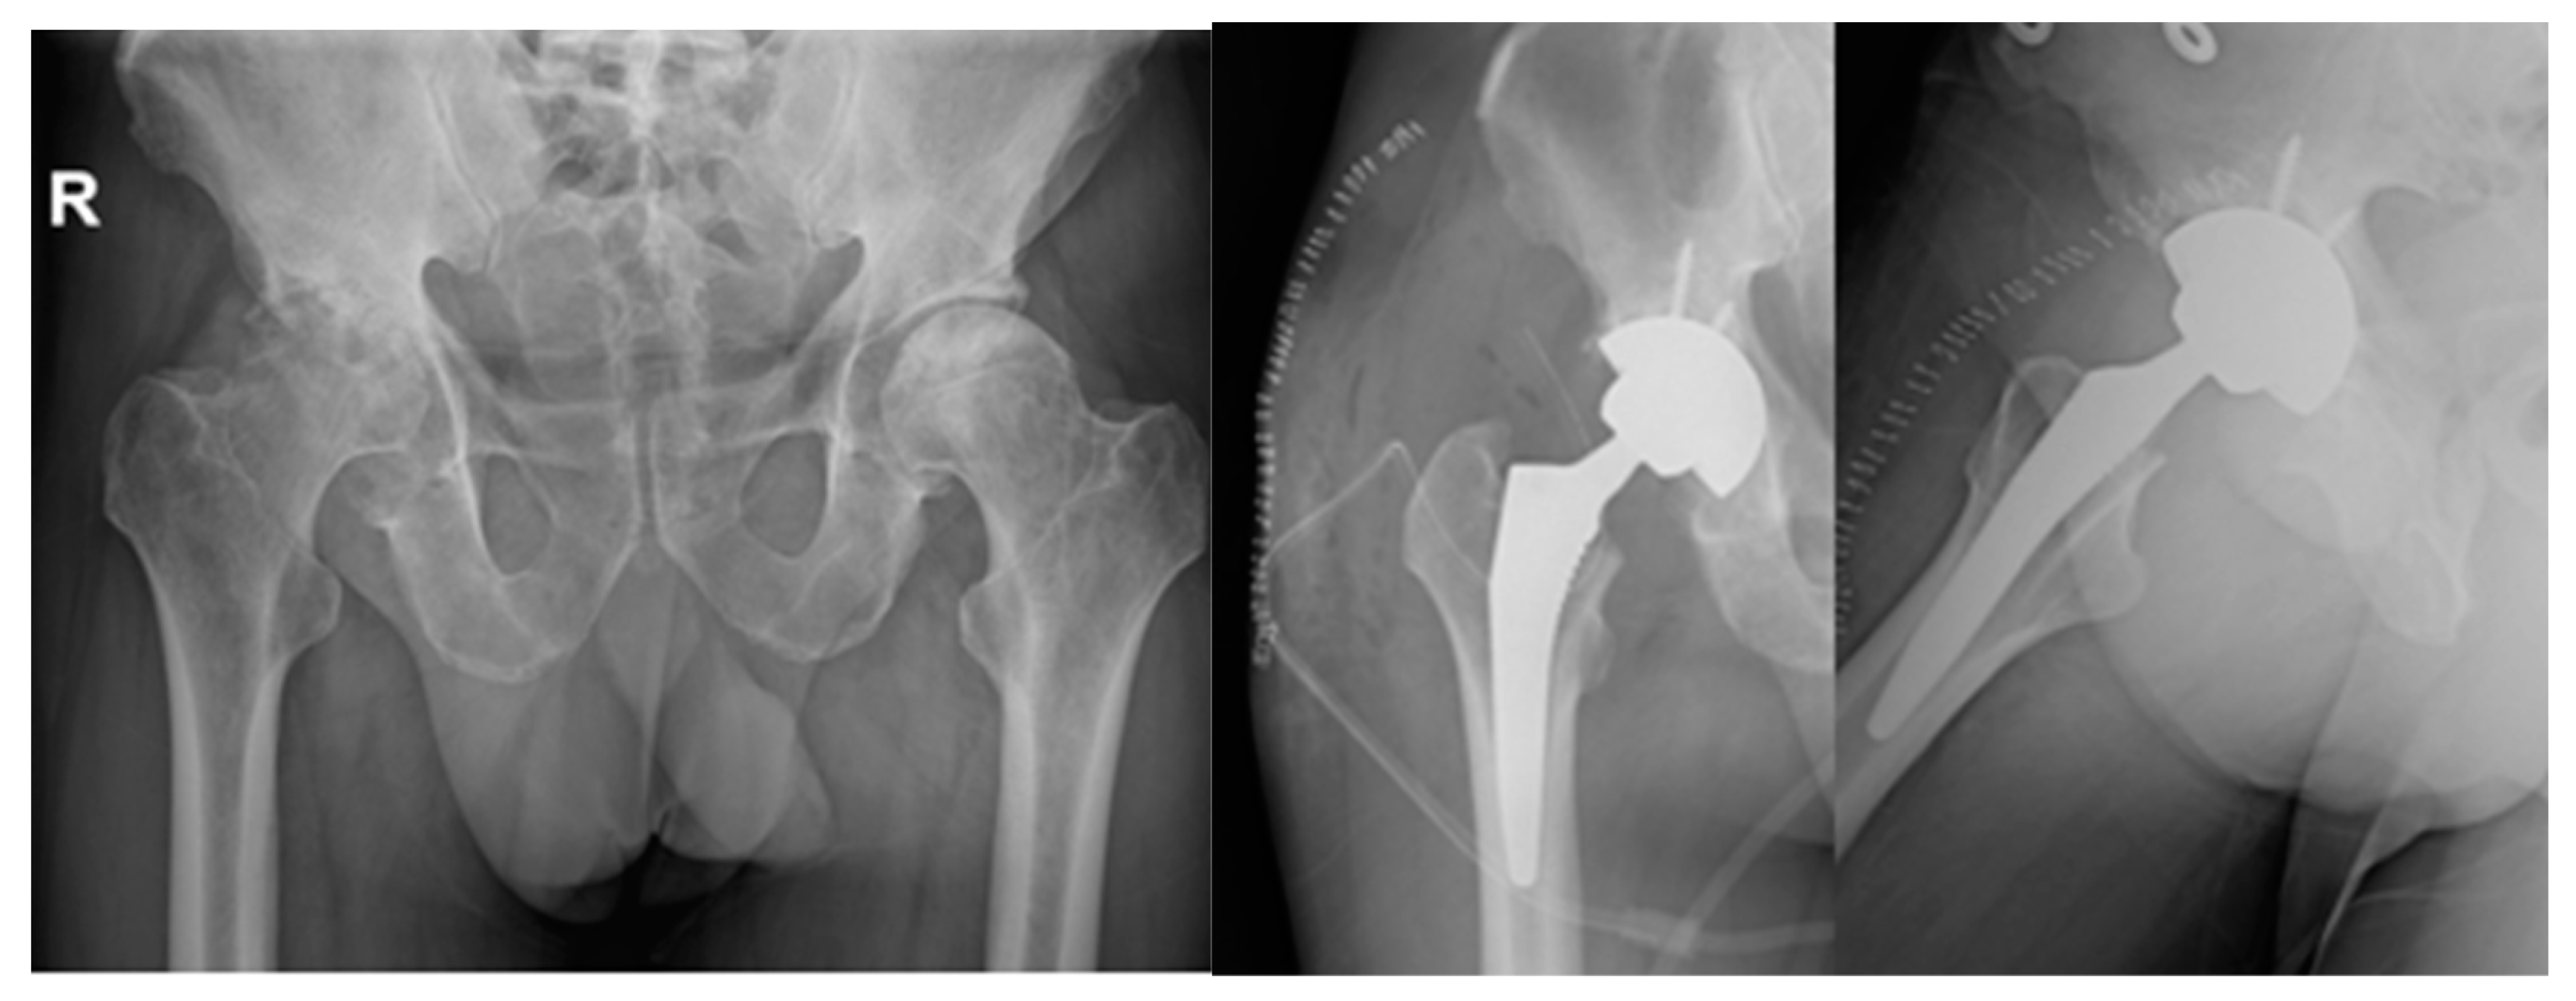

Figure 4. MRI of bilateral AVN of humerus head (Right).